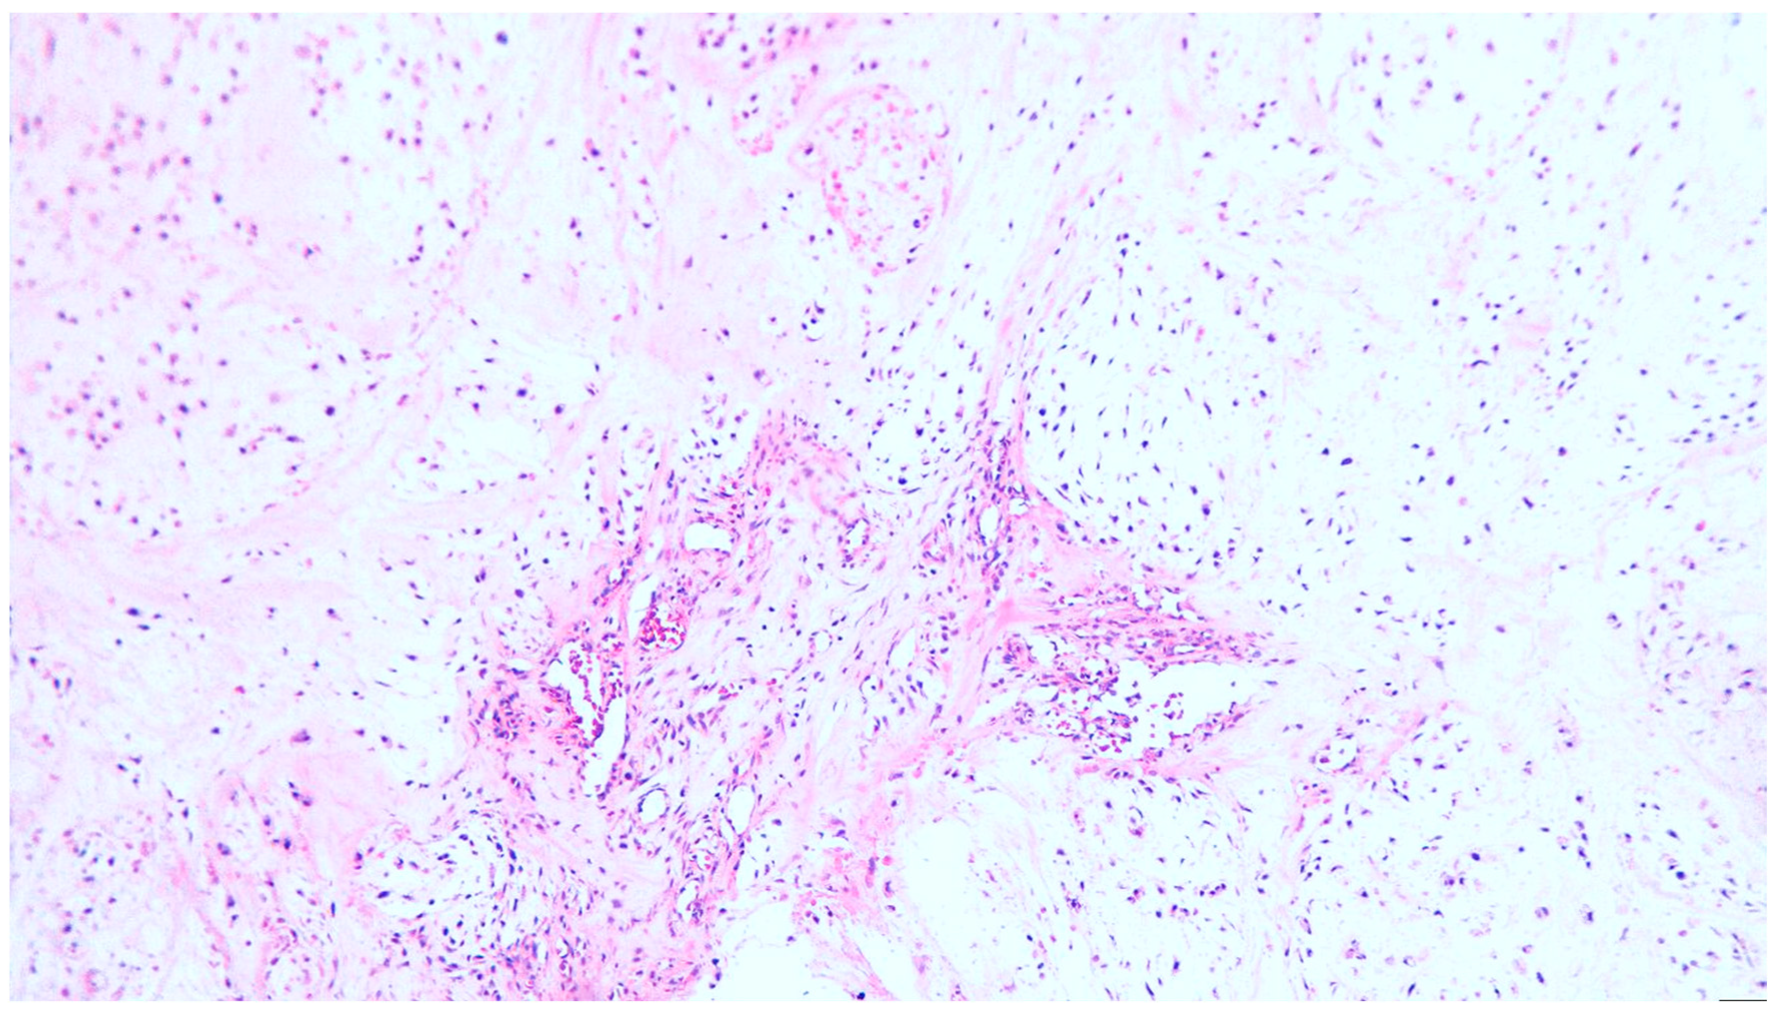

2. Clinical Case